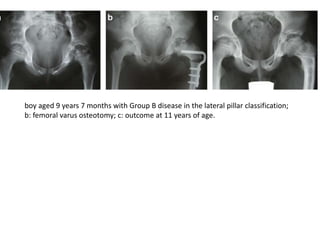

boy aged 9 years 7 months with Group B disease in the lateral pillar classification;

b: femoral varus osteotomy; c: outcome at 11 years of age.

boy aged 9years 7 months with Group B disease in the lateral pillar classification; b: femoral varus osteotomy; c: outcome at 11 years of age.